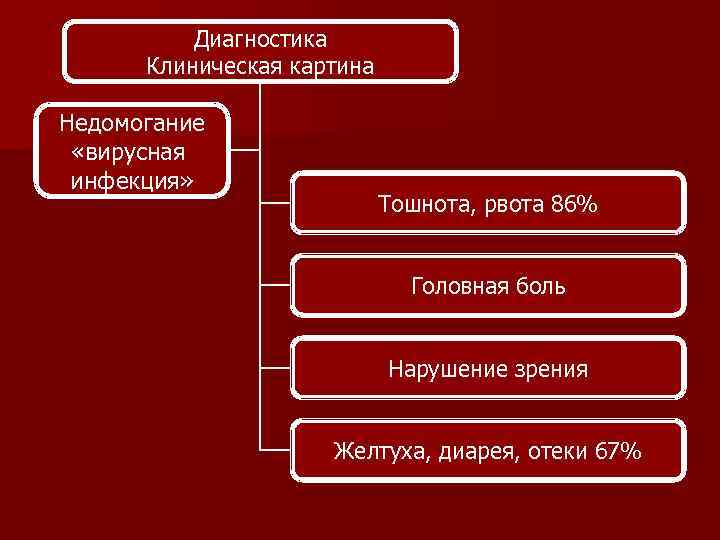

Диагностика Клиническая картина Недомогание «вирусная инфекция» Тошнота, рвота 86% Головная боль Нарушение зрения Желтуха, диарея, отеки 67%

Диагностика Клиническая картина Недомогание «вирусная инфекция» Тошнота, рвота 86% Головная боль Нарушение зрения Желтуха, диарея, отеки 67%